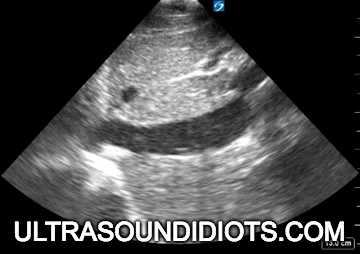

Echo Subcostal Exams